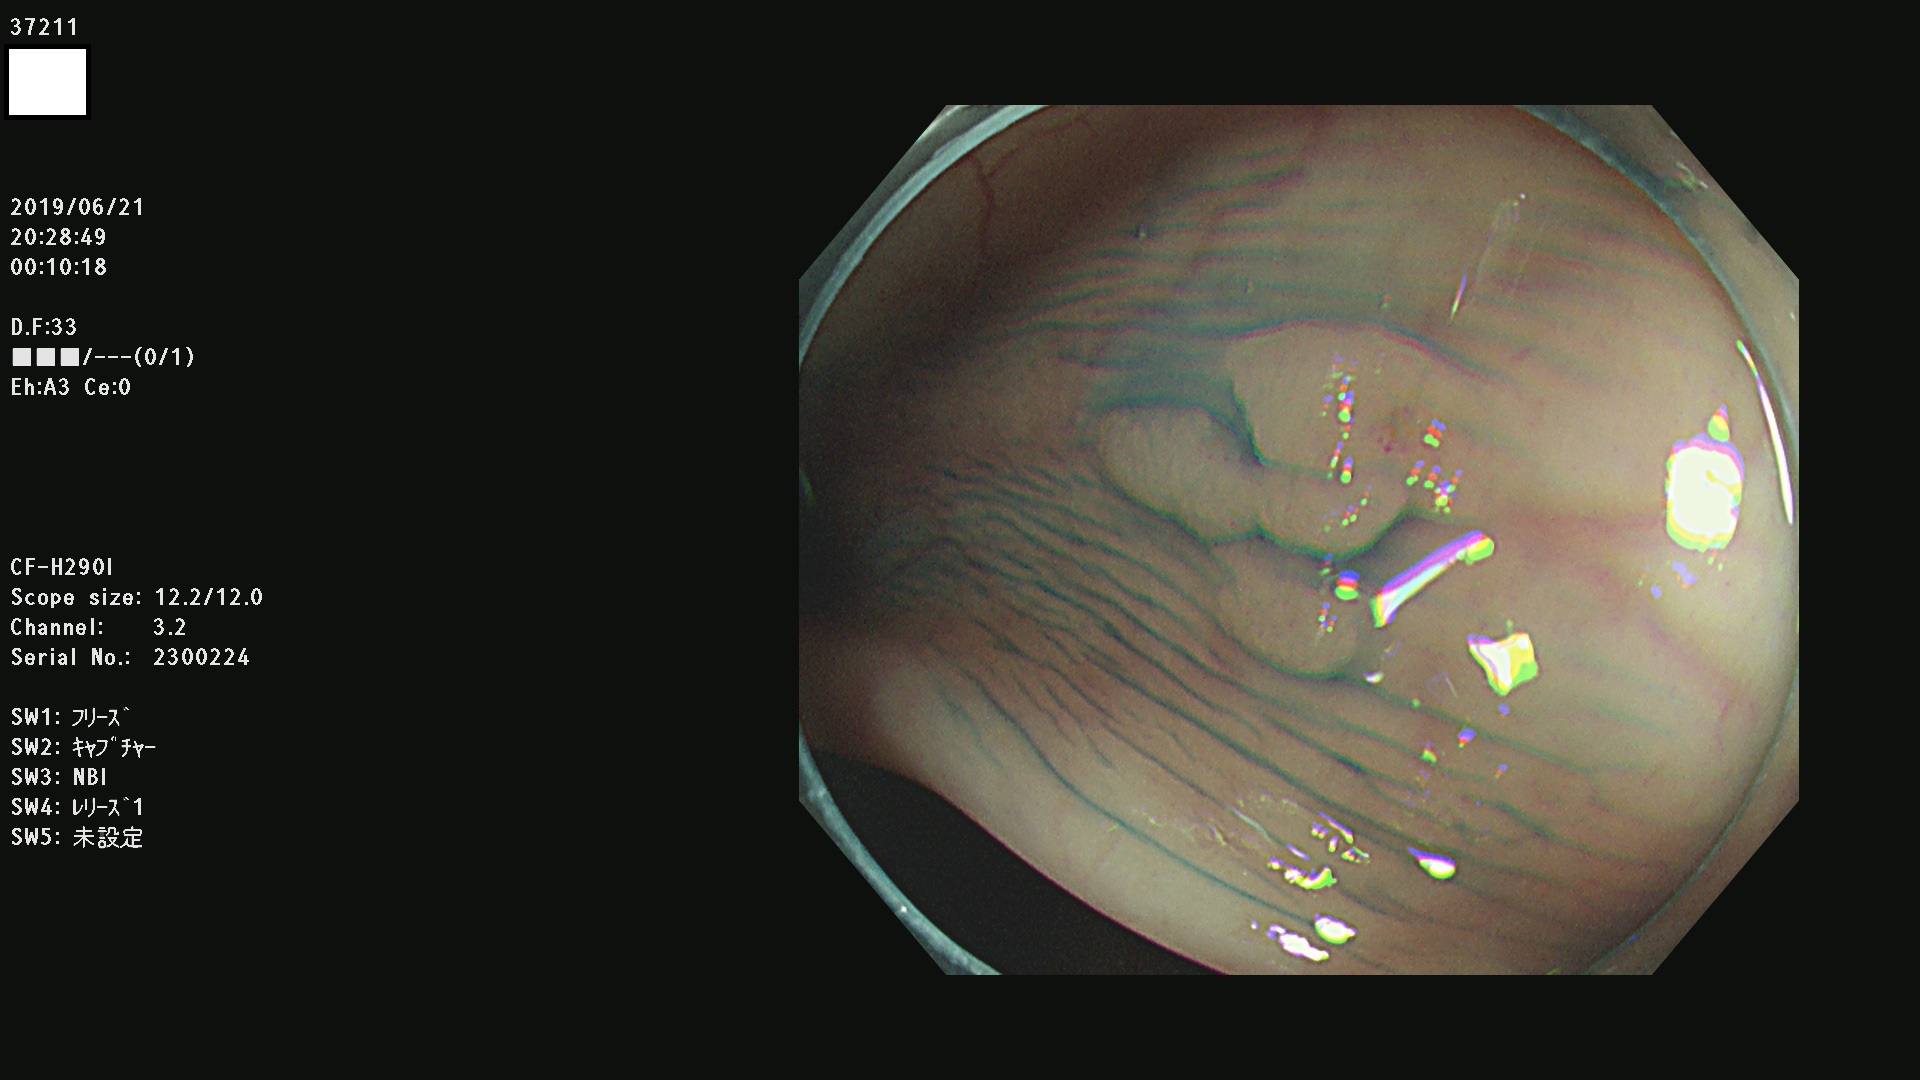

37200 37203 37204 37207 37208 37209 37210 37211 37212 37213 37214 37215 37216 37217 37220 37221 37222 37224 37225 37228 37229 37230 37232 37233 37234 37235 37236 37238 37241 37242 37243 37244 37245(SSAPのみ) 37247 37249 37250 37251 37252(SSAPのみ) 37254 37256 37257 37258 37259 37260(SSAPのみ) 37261(SSAPのみ) 37262 37263 37264 37265 37266 37267 37268(SSAPのみ) 37269 37271 37273 37274 37276 37277 37278 37279 37280 37281 37282 37284(SSAPのみ) 37285 37286 37288 37289 37290 37292 37293 37295 37296 37297(SSAPのみ)

発見困難で危険性の高い平坦型病変(上記100名より抽出)